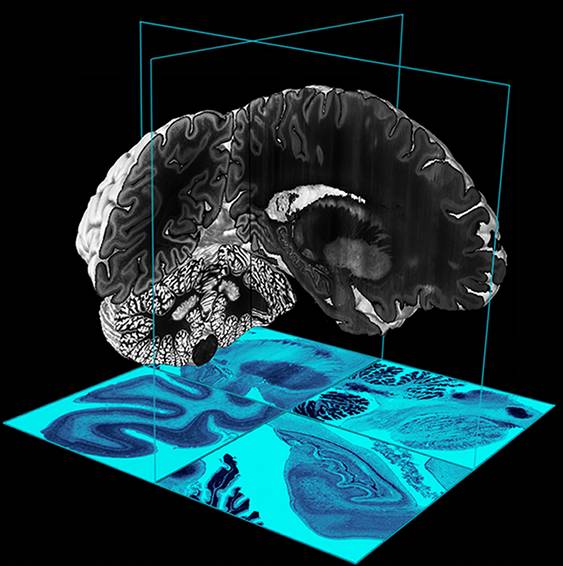

Tra i temi dell'esame di maturità, quest'anno spiccava il cervello. Negli stessi giorni, la rivista scientifica Science annunciava la realizzazione della prima mappa in 3 dimensioni di questo organo. Per ottenerla i ricercatori hanno sezionato il cervello di una donna deceduta, in più di 7 mila fettine di 20 micrometri di spessore. Questo risultato permetterà di studiare la forma e le funzioni del nostro cervello in modo estremamente approfondito. Le neuroscienze si confermano in questo momento la disciplina di maggior successo nel mondo scientifico e nell'interesse dei media.